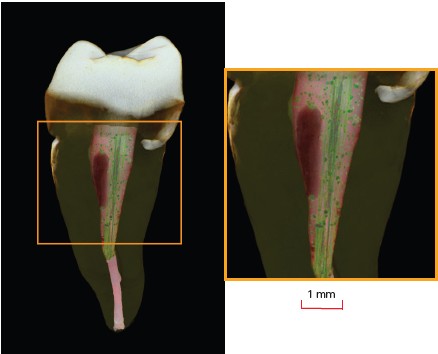

Micro-CT provides 3-dimensional imaging on a small scale with very high resolution, with no sample preparation or slicing. The internal structure of tissue and the internal adaptation of materials to surfaces can be studied non-destructively. Micro-CT has become a standard imaging tool in dental research for many applications, including restorative dentistry (Figure 1), endodontics, tissue engineering, and research on mineral density of hard tissues and bone growth.

The X4 POSEIDON modular micro-CT system is equipped with a high resolution sCMOS detector that is ideal for examination of the microstructural integrity of teeth and dental restorations (Figures 2, 3 and 4). The X4 produces high-quality images from the outer to innermost structure of the tooth. In restorative dentistry, a key application is the study of the marginal and internal fit of filling materials, where research shows that the material type significantly influences the adaptability of the restoration, with some materials achieving lower marginal and internal gap values.

The system provides a non-invasive, reproducible, and accurate technique for the qualitative and quantitative assessment of teeth and dental materials. The software enables users to extract data on the mineral density of tooth structure and tooth-restoration interfaces. Data can be shown in 2D or 3D renderings, and slices can be produced in any plane.